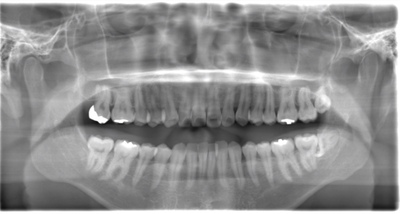

CASE 1

| 年齢・性別 | 30代・女性 |

| 主訴 | 左右に分けて親知らずを抜きたい、できれば痛くなく抜きたい |

| 親知らずのはえ方 | 完全に出ていてまっすぐはえている |

| 抜歯期間 | 15分 |

| 抜歯費用 | 約2,000円(保険内) |

| 抜歯内容 |

何度か虫歯になり痛みはないが早めに抜きたい。 完全に頭が出ているため歯ぐきを切ったり骨を削らずに抜歯しました。 根の形も単純なため抜歯自体は5分もかからず上下ともに終わりました。 術後痛みや腫れも出ていません。 抜歯後は感染をしやすいため必ず抗生物質を飲み切ってください。 |